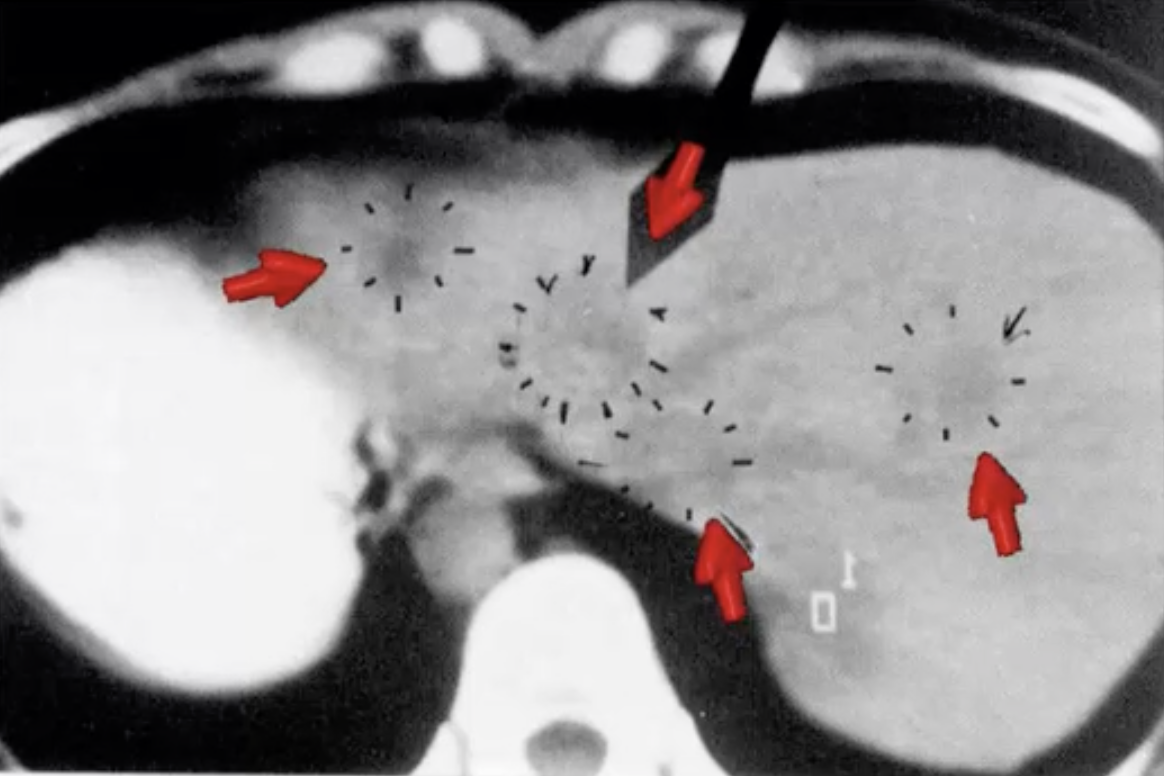

Transition to Healing: The Edema Phase

Upon the resolution of the underlying conflict (perhaps days, months, or years after the initial shock, depending on circumstance), the brain undergoes a remarkable shift from conflict management to the post-conflict healing phase. This transition is marked by the development of edema in the brain relay, signaling the beginning of the body’s restorative process. The edema represents the brain’s efforts to heal itself.

Simultaneously, the corresponding organ, which had been in a state of adaptation to manage the conflict (with cell growth, cell loss, or functional change), enters the inflammatory restoration phase. This phase is characterized by inflammation, a natural part of the healing process, signifying the organ’s attempt to return to its pre-conflict state of health. The presence of inflammation, rather than being a sign of further disease, is a positive indication of the body’s efforts to heal and restore normal function.